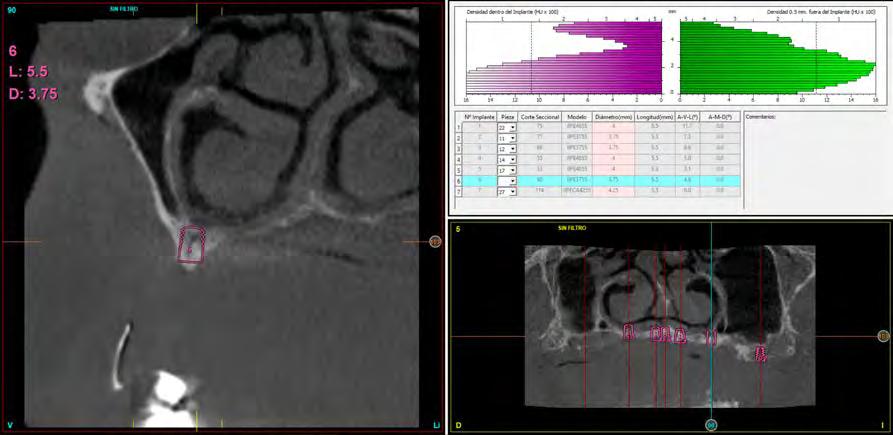

Fueron reclutados pacientes en los que se insertaron implantes de 5.5 mm de longitud p ara realizar rehabilitaciones de arco completo, desde enero a noviembre de 2020 en un único centro clínico (Clínica Dental Eduardo Anitua, Vitoria, Álava). Todos los pacientes fueron estudiados antes de la inserción de los

implantes mediante modelos diagnósticos, exploración intraoral y realización de un TAC dental (cone beam) analizado posteriormente mediante un software específico (BTI-Scan III). Antes de la inserción de los implantes se utilizó una premedicación antibiótica consistente en amoxicilina 2 gramos vía oral 1 hora antes de la intervención y paracetamol 1 gramo vía oral (como analgésico). Posteriormente los pacientes prosiguieron con un tratamiento de amoxicilina 500750 mg vía oral cada 8 horas (según peso) durante 5 días.

Para la estimación de la pérdida ósea marginal se tomó como referencia una longitud conocida en las radiografías (longitud del implante) para calibrar de ese modo las mediciones realizadas en estas radiografías. A partir de la calibración el software

Figura 1. Diámetros y longitudes incluidos en el estudio según su posición.

utilizado calcula las mediciones reales (Digora for Windows, SOREDEX Digital Imaging systems). La pérdida ósea crestal marginal se calculó midiendo desde el hombro del implante hasta el primer sitio donde el contacto hueso implante fuese evidente. La referencia para comparar los registros radiográficos y de este modo estimar la pérdida ósea producida en cada uno de los pacientes fue la radiografía realizada en el momento de inserción de la prótesis. Esta radiografía se utilizó por

lo tanto como punto de partida para todas las medidas posteriores.

El implante fue la unidad de análisis para la estadística descriptiva en cuanto a la localización, dimensiones del implante, y mediciones radiográficas. El paciente fue la unidad de medida para el análisis de la edad, sexo y la historia médica. La variable principal fue la supervivencia del implante y como variables secundarias se registraron la pérdida ósea mesial y distal y la aparición de complicaciones protésicas posteriores a la carga.

Las variables cualitativas se describieron mediante un análisis de frecuencias. Las variables cuantitativas se describieron mediante la media y la desviación estándar. La supervivencia de los implantes se calculó mediante el método de Kaplan-Meier. Los datos fueron analizados con SPSS v15.0 para windows (SPSS Inc., Chicago, IL, USA) Se estableció una comparación de medias entre la pérdida ósea crestal mesial y distal en función de la localización anatómica (maxilar-mandibular) mediante la prueba de T-Student.

completas superiores y 3 inferiores. Todos los implantes presentaron una longitud de 5.5 m m, con diámetros comprendidos entre los 2.5 y los 5.5 mm. Las posiciones de los implantes corresponden a distribuciones biomecánicas para la realización de prótesis completas tanto en el maxilar como mandíbula (incisivos, premolares y molares). Los diámetros y longitudes de los implantes incluidos en el estudio en función de

su posición se muestran en la Figura 1.